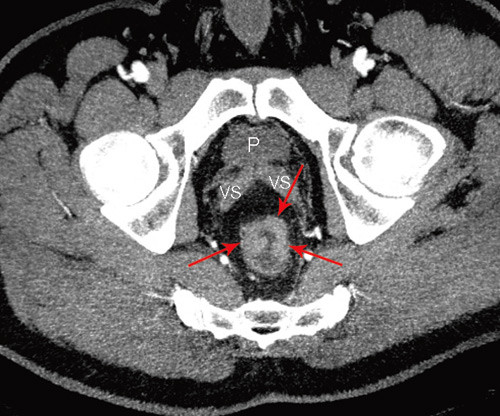

Multidetektor-CT

Bruk av CT i utredningen av fjernmetastaser ved kolorektal kreft er en godt etablert metode. CT-undersøkelsens rolle i den lokoregionale utredningen av rectumcancer er betydelig mer usikker. Studier fra de senere år har vist relativt dårlige resultater når det gjelder evaluering av perirektal tumorspredning, med en nøyaktighet på 52 – 74 % (6, 7, 12). Med MDCT-maskiner med minst 16 kanaler har man fått muligheten til å ta tynne bildesnitt som kan rekonstrueres i alle plan med samme gode bildekvalitet (fig 1, fig 2). Slik kan man få bilder parallelt og perpendikulært til tumors lengdeakse, analogt til MR-undersøkelsen. Det er vist at bruken av slike rekonstruerte bilder signifikant bedrer evalueringen med multidetektor-CT (13). Det finnes få studier der man har sammenliknet MDCT-undersøkelse med andre metoder ved rectumcancer, men resultatene så langt synes å være lovende (14) – (17).

Man venter snart resultater fra en ny, stor multisenterstudie i Nederland der bruk av CT-undersøkelse ved rectumcancer evalueres. I en nyere artikkel av Beets-Tan og medarbeidere refereres det til preliminære resultater som viser at MDCT er likeverdig med MR i øvre/midtre del av rectum, mens MR er overlegen i nedre del (18). I forhold til MR har CT dårligere evne til å skille bløtdelssjiktene fra hverandre i dette området, hvor subtile detaljer som 1 – 2 mm infiltrasjon kan skille en T2-tumor fra en T4-tumor (fig 3).